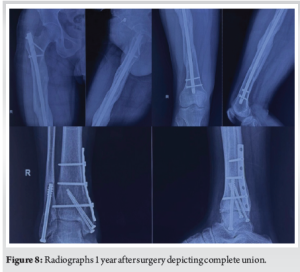

The patient had an uneventful post-operative course. An immediate post-operative radiograph depicted satisfactory alignment (Fig. 6). He was advised of early mobilisation with weight-bearing limitations . Radiographs 3 months after surgery showed signs of fracture healing and satisfactory alignment (Fig. 7). The patient continued physiotherapy to regain range of motion and strength in the injured limb. Radiographic evaluation 1 year after surgery confirmed complete fracture union (Fig. 8). The other fractures–the patella, acetabulum, cuboid, and bimalleolar–had also appropriately healed. The patient returned to his pre-injury activity level without limitations and reported no persistent pain.

Segmental femur fractures with four fracture lines and five fracture segments have been reported twice in the literature [8,9]. However, they included neck femur fractures or distal femur fractures. This case illustrates an exceedingly rare injury pattern: A triple-segmental shaft femur fracture, which has never been documented in the literature. The main challenges are ensuring stable fracture fixation, maintaining the blood supply to the fracture segments, and shielding the surrounding soft tissues from additional harm during fixation. In addition, when treating such complex femur fractures, complications like non-union, infection, or malunion are frequent. Intramedullary nailing was selected as the fixation technique because it minimises tissue disruption while offering stable fixation [10]. A speedier recovery was made possible by early mobilisation and rehabilitation. Furthermore, the patient’s concomitant fractures, including a bimalleolar fracture, were successfully managed, highlighting the necessity of an all-encompassing treatment plan. This case emphasises the significance of a customised approach in managing polytrauma patients.